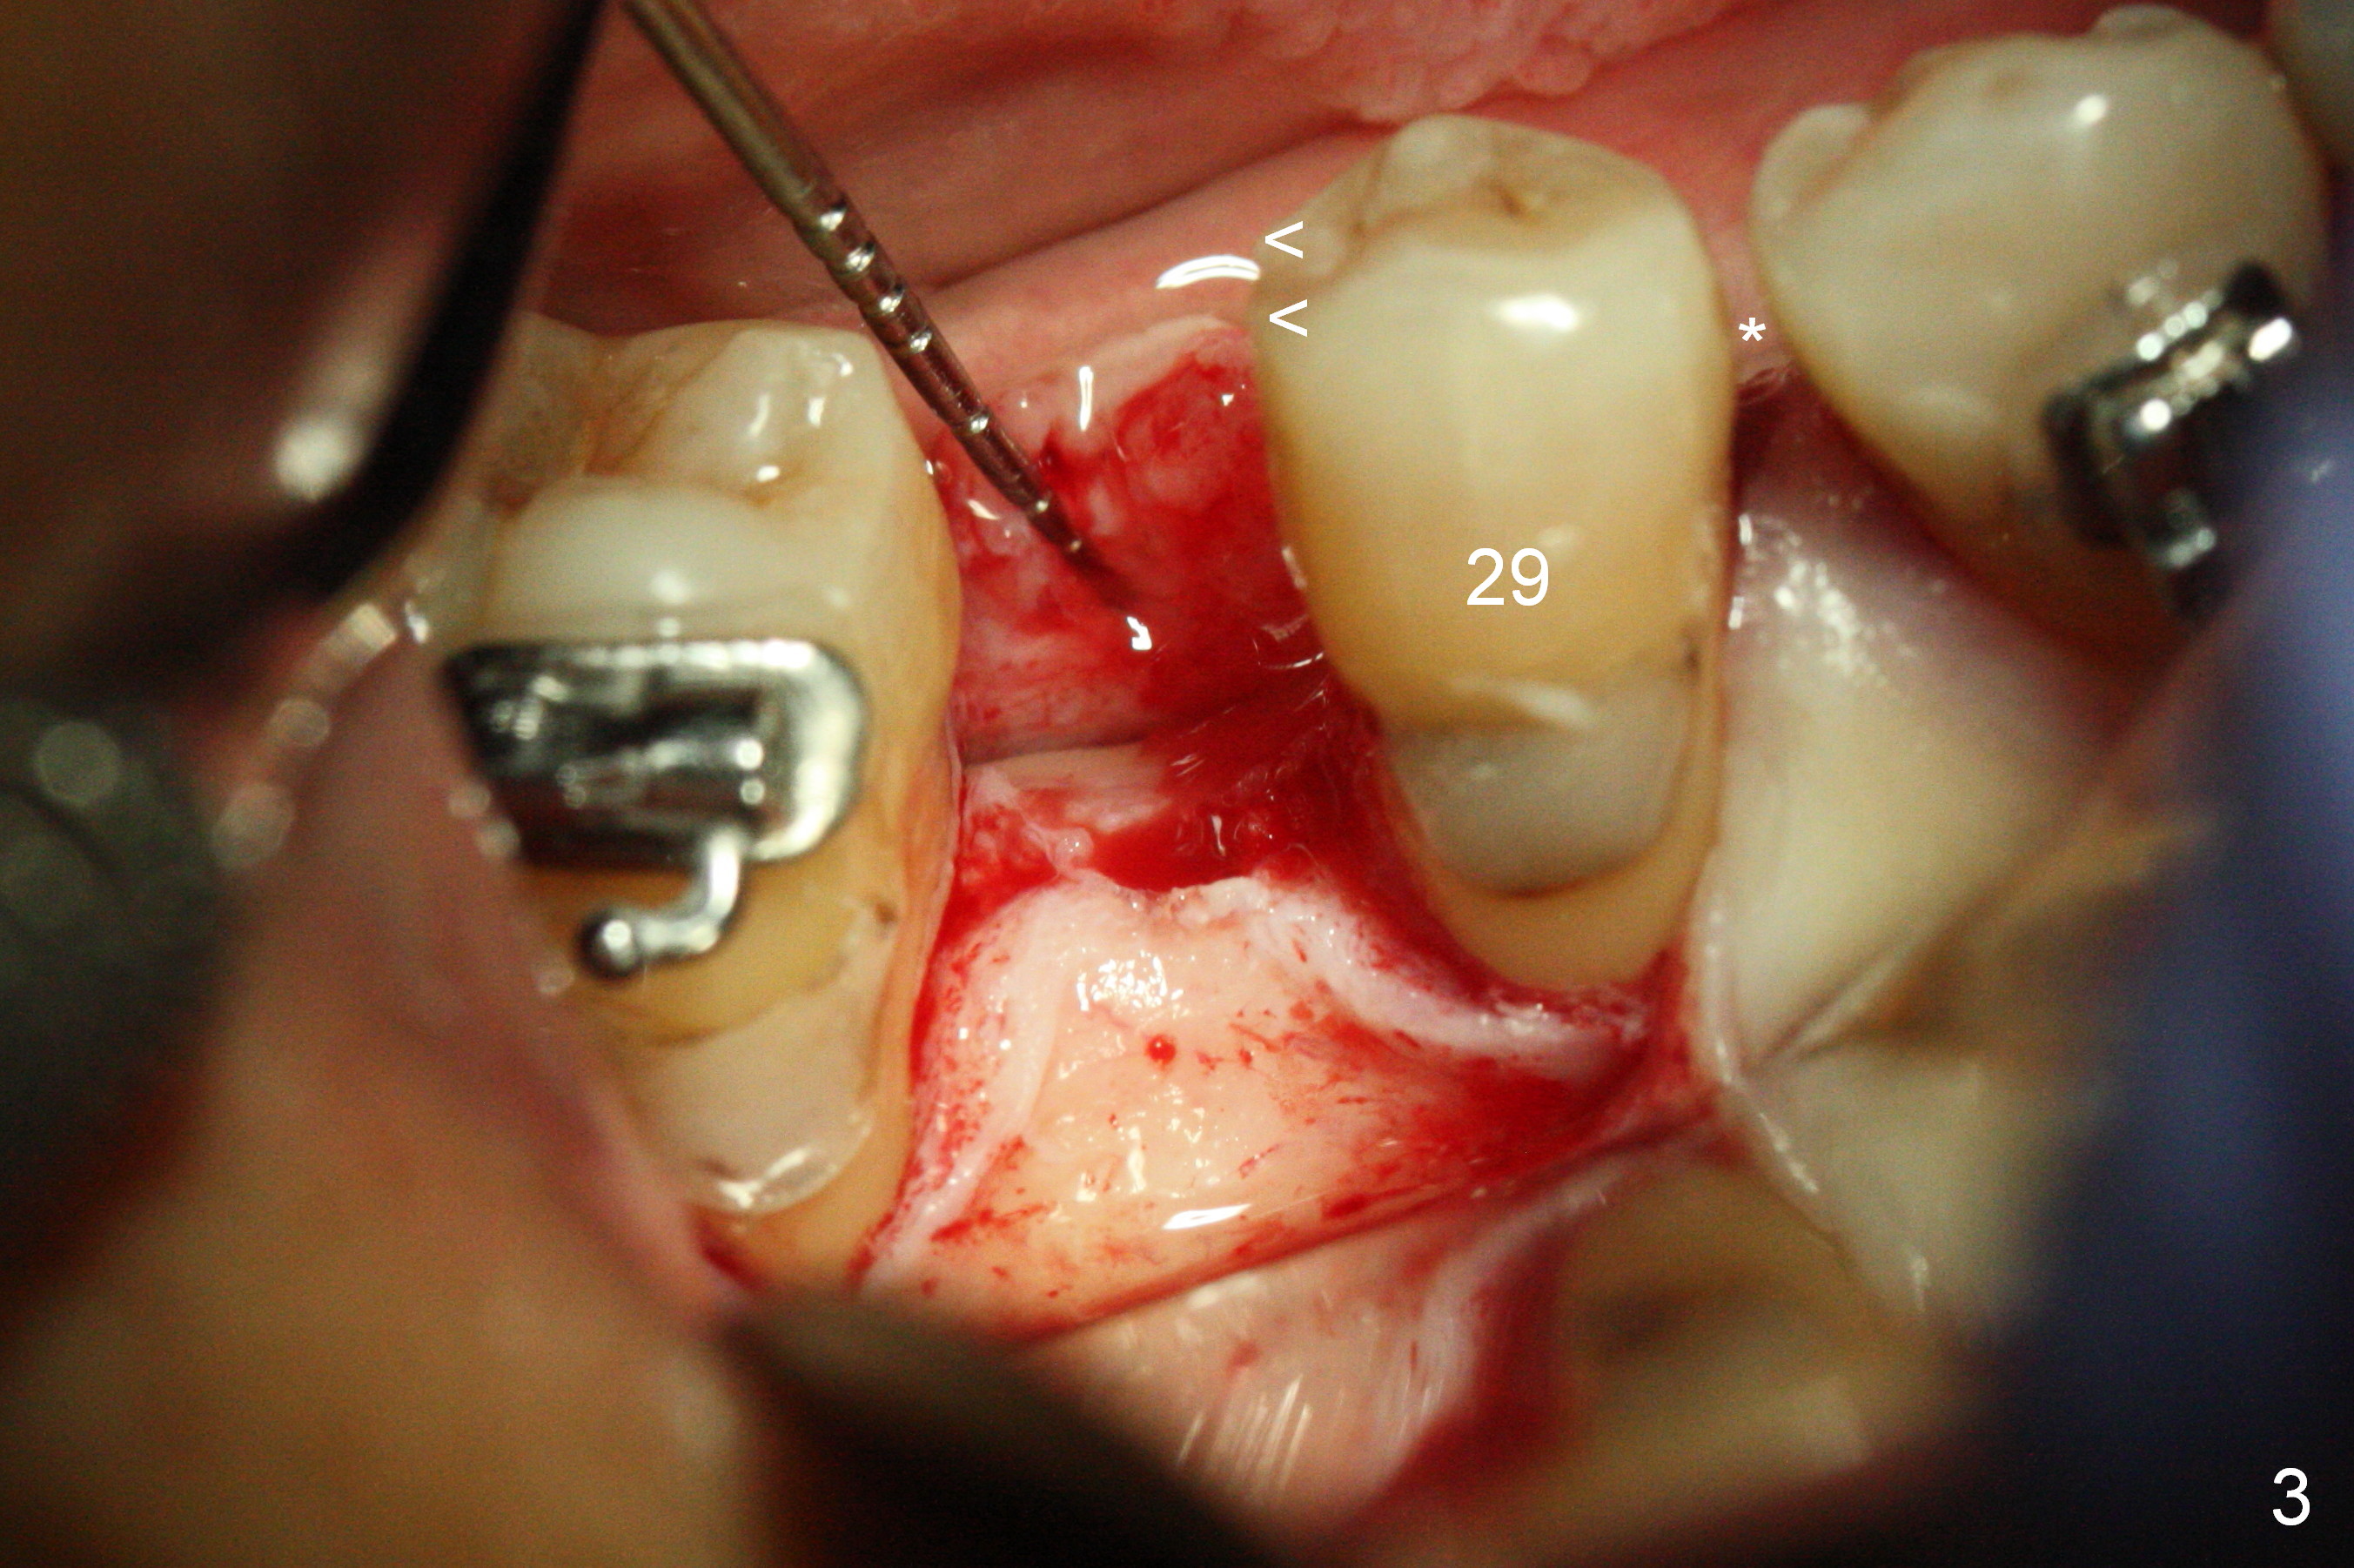

Mesialization of the tooth #29 consists of open coil spring distal (Fig.1 ^) and closed coil spring mesial (^^^). Due to limited time and incompliance, the mesialization is incomplete (Fig.3 *). Total treatment lasts 1 year. The mesial surface of the #29 (Fig.3 <) and the distal surface of #31 are trimmed before incision. The mesiodistal width increases from 5 mm to 6 mm. In fact the ridge is not too narrow buccolingually when an incision is made (Fig.3). There is bone buccal and lingual to a 2.5 mm osteotomy (Fig.3) after adjustment of its initial one with 1.2 mm pilot drill (Fig.2 (red dashed line: the Mental Loop). A 3x12(2) mm 1-piece implant is placed (Fig.4) with insertion torque > 40 Ncm. GBR is also done to increase ridge width.